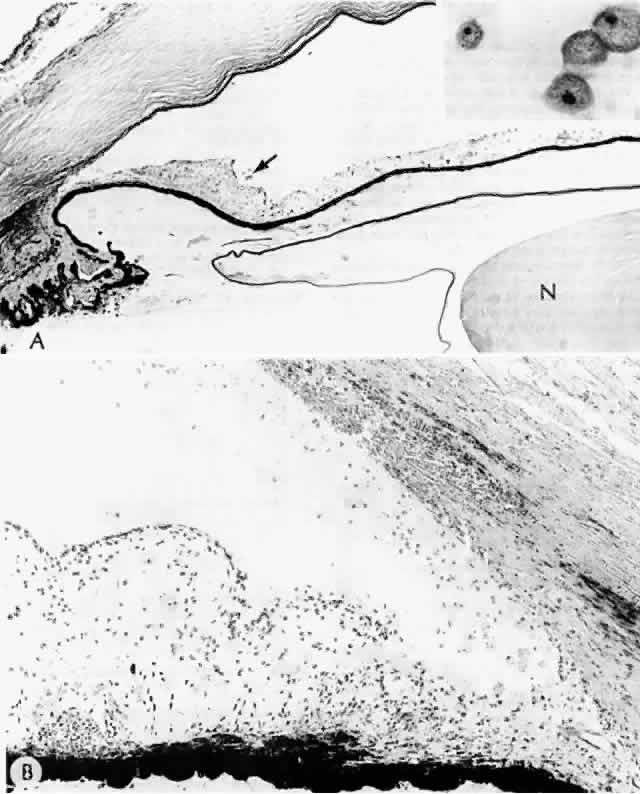

Histologic examination shows an unequal splitting of the anterior capsule (Fig. 1). Electron microscopic examination shows that the lens capsule is laminated and the anterior layer or layers are split free.29 The free portion is quite thin, and it can be rolled or folded over.27

Fig. 1. True exfoliation of the lens capsule. The anterior lens capsule is split and floats away from the rest of the lens (arrow). The subepithelial disruption is artifact. (H & E, magnification × 234; Courtesy of Dr. W.R. Green, Baltimore, MD)

Fig. 9. A. Dark nucleus floating within a liquefied, “milky” cortex settled inferiorly because of gravity. B. Hypermature cataract characterized by a wrinkled anterior capsule (a). No cortex is present (it has liquefied and leaked out); only the nucleus (N) is present. Homogeneity of the nucleus marks it as cataractous. A calcium oxalate crystal (arrow) is present in the nucleus; p' = posterior capsule of lens. A calcium oxalate crystal can be seen within the nucleus before (C) and after (D) polarization. (A, courtesy of Dr. G. Naumann, × 100; D, polarized, H & E × 100)